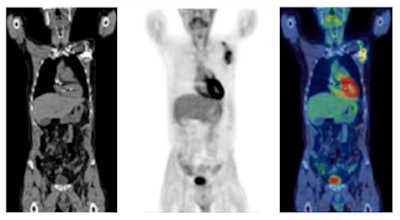

F-18 FDG PET/CT in the assessment of an infected cardiac pacemaker. (All figures courtesy of RCR)

F-18 FDG PET/CT in the assessment of an infected cardiac pacemaker. (All figures courtesy of RCR)The guidelines comprise an up-to-date summary of relevant indications for the use of PET/CT, where there is good evidence that patients will benefit from improved disease assessment, resulting in altered management and improved outcomes, according to the authors.